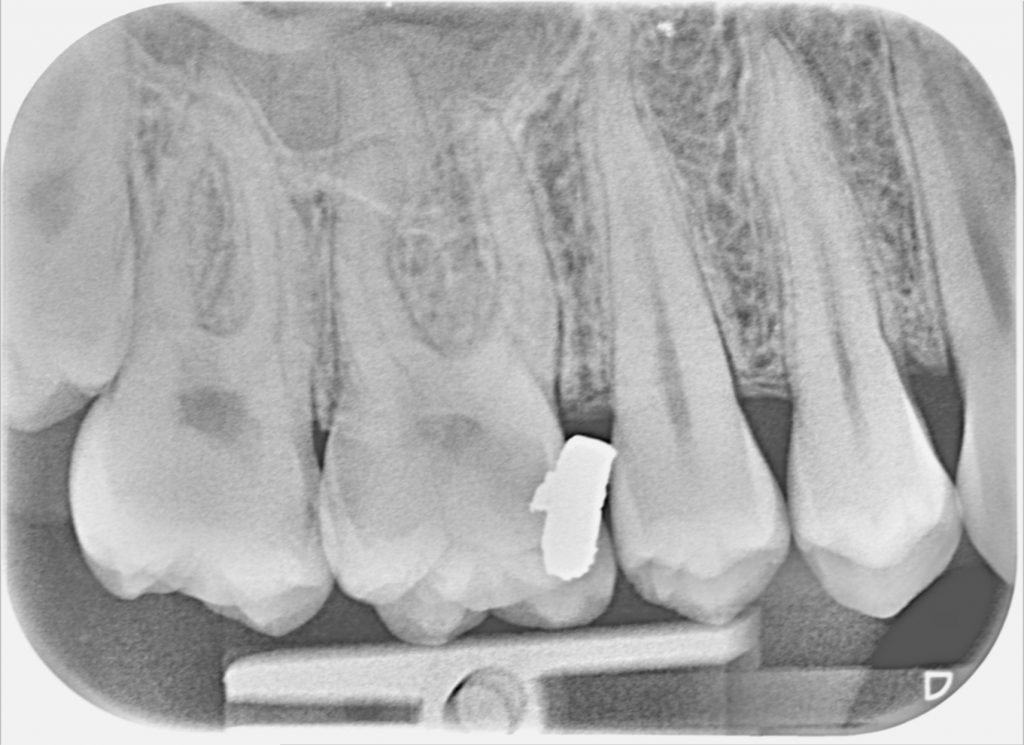

Probing pits and fissures can be a controversial subject. Some find the tactile feedback (sticky, retentive pit or fissure) from the probe useful. But studies have shown that a sticky feeling with a sharp explorer may not be the best identifier of active caries, and could itself irreversibly damage tooth structure that may have responded to remineralization techniques. Pit and fissure caries do not appear so readily and clearly on radiographs when compared to interproximal caries.

Note the shadowing around the fissure system of the second premolar and first molar, compared to the first premolar.

SMOOTH SURFACE CARIES

For the most part smooth surface interproximal caries is picked up during routing radiographs. 30% or more of the mineral structure needs to be lost before a carious lesion is distinguishable on a radiograph. A radio-opacity just below the interproximal contact suggests caries. Once found it can be difficult to accurately assess whether a lesion is active or inactive. Lesions may be active if the patient has an overall high caries risk, the lesion was not present at a previous exam, or the caries extends into the dentin. Lesions may be inactive if successive bitewing radiographs show no lesion progression, or the patient has a low caries risk.